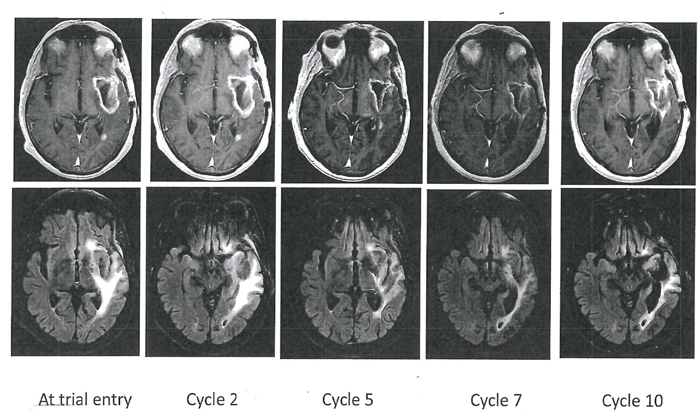

Patient 5, a 69 year-old man with a recurrent GBM (IDH1/2 wild type, methylated MGMT promoter), had tumor progression on a clinical trial consisting of IMRT/TMZ, then TMZ and vorinostat (a histone deacetylase inhibitor). He developed grade 3 neutropenia on AXL1717, 300 mg bid after 2 cycles. Thereafter, the dose was reduced to 215 mg bid which he tolerated well and had stable clinical and imaging disease of left temporal and periventricular lesions (see serial MRIs, patient 5 in Figure 1). Additionally, T2 FLAIR sequences showed decreased edema during the serial MRI examination. Evaluation of his MRI imaging demonstrated re-enhancement of a pre-existing portion of the tumor in the left periventricular region suggesting tumor progression after cycle 7. He was taken off study after 12 months treatment (cycle 10) although clinically stable. He died 8 months later of disease progression.

Figure 1: Axial T1-weighted contrast-enhanced (top row) and T2-FLAIR images (bottom row) in Patient 5. This patient had a left temporal glioblastoma illustrated as a cystic lesion with a rim of contrast-enhancement. This cavity was stable throughout the serial MR examinations and T2-FLAIR showed decreased edema. Four smaller contrast-enhancing lesions (out-of-field) were also stable throughout the study in the left temporal and left periventricular region. After cycle 7, a small new contrast-enhancing lesion appeared in the left temporal region and represented progressive disease.